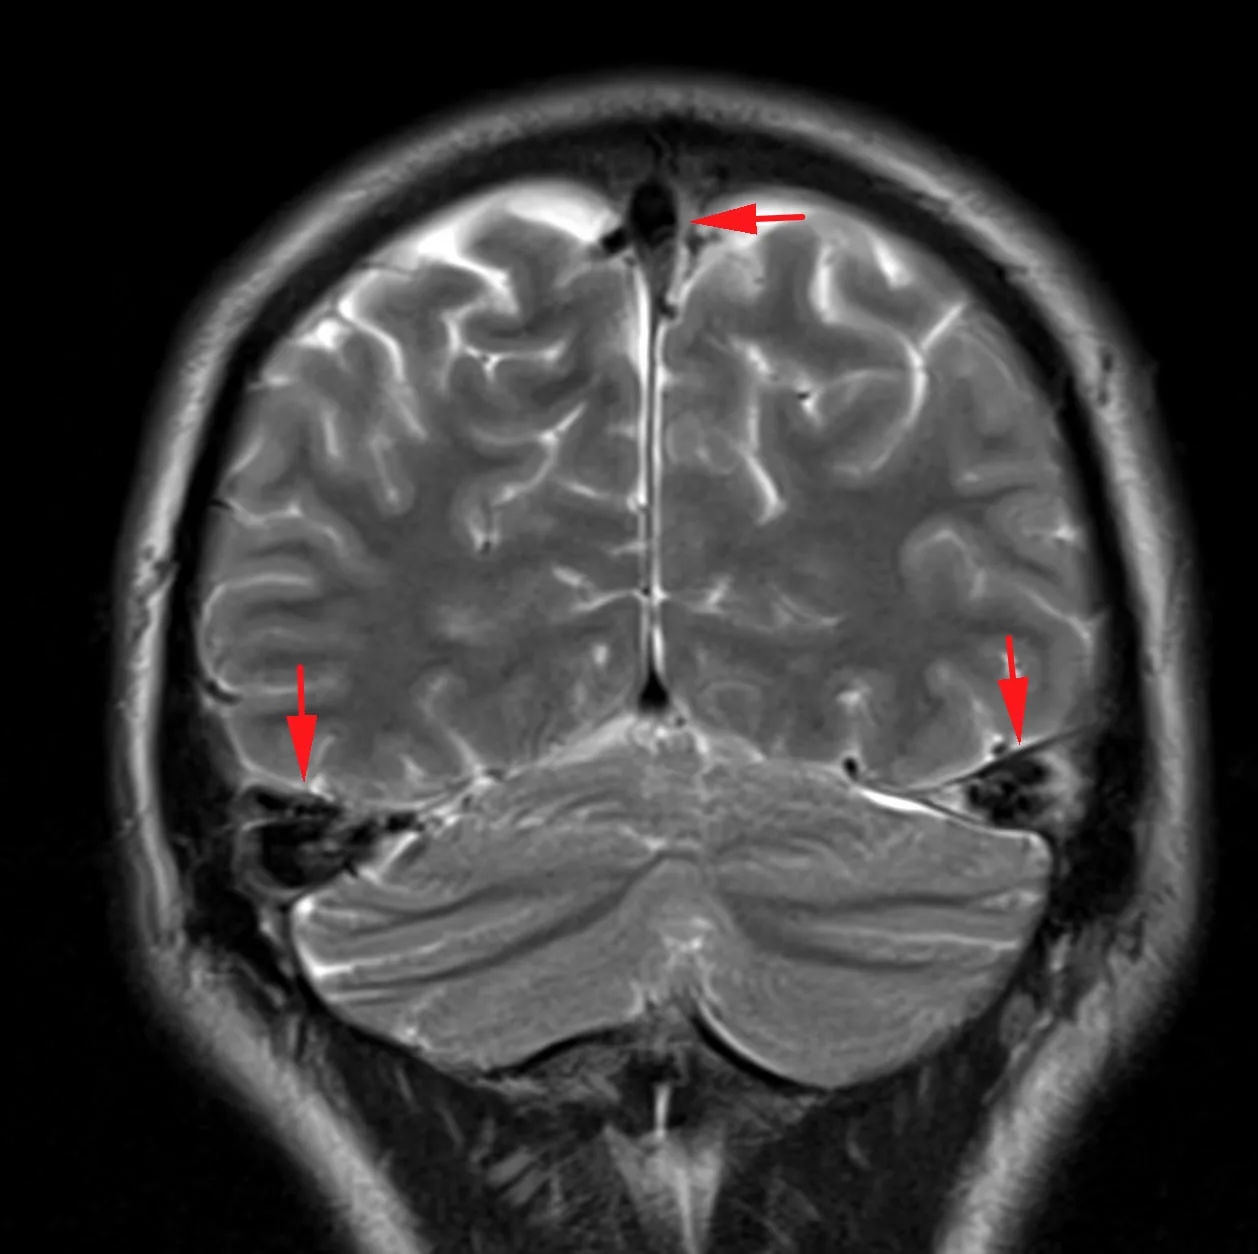

Наконец-то я увидел это воочию! Киста полости Верги, промежуточного паруса, осложнённая гидроцефалией. Из анамнеза: Низкое артериальнео давление, нарушение речи, затуманенное сознание, головная боль, головокружение, в 1989 году перенёс менингит.

А Вы видали такое? Я впервые вижу, раньше только читал в литературе.